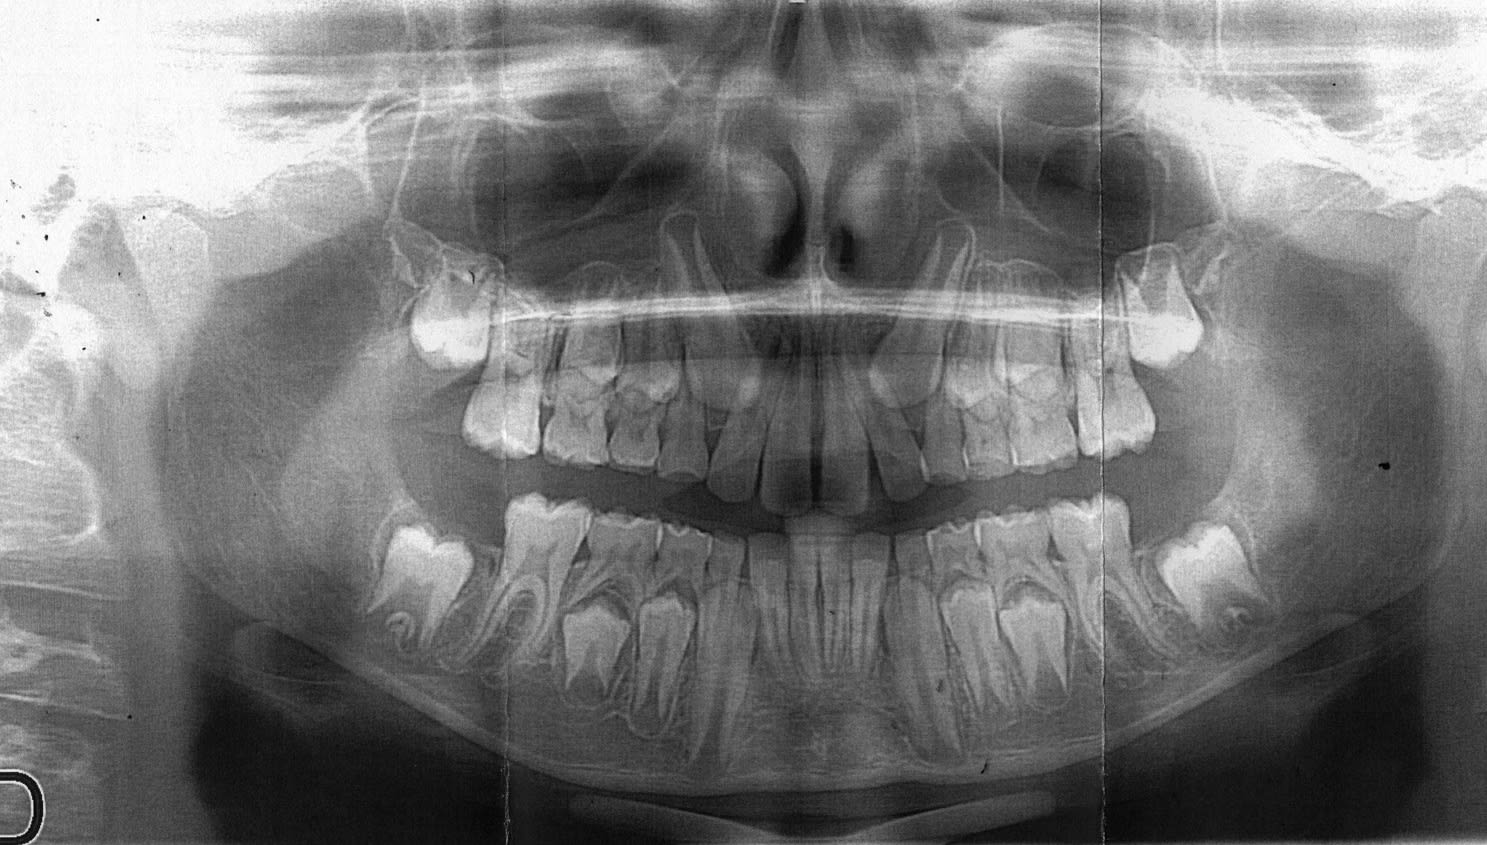

J'ai un petit cas de conscience pour un jeune patient de 10 ans.

Le gamin a été envoyé il y a 2 ans chez mon odf préféré: à l'époque, classe II 1 avec interposition labiale, un activateur de croissance est actuellement en cours et doit être déposé dans 1 mois, un multibague est prévu en denture définitive.

La dite consoeur me demande de virer 53 63 "pour favoriser l'évolution de 13 23."

Je ne pense pas que cela va "favoriser l'évolution de 13 23" dans la mesure ou ça va en éventail de la 12 à la 22.

Ils disent que c'est parfois intéressant, ils insistent sur l'intérêt de maintenir l'espace. Je te colle leur image, elle est sympa, est quasi similaire à la tienne!

Je suis d'accord sur le fait de ne pas extraire les canines temporaires, en regard de leur inclinaison et de leur position je n'en vois pas l'intérêt.

-Dans le cas présent, je ne vois aucun indice me laissant envisager un risque de futures canines incluses. Et il faut bien dire que la nature fait généralement bien les choses, que les dents tombent quand elles doivent tomber, et que j'en ai un peu marre du surtraitement sous toutes ses facettes.

Je suis ortho et les indications d'extractions des canines temporaires sont indiquées dans ton cas et réduisent le risque d'inclusion des canines.

Pour les références de mémoire l'article est d'Ericson et Kurol et tu trouveras également les références dans le Profitt.

Plus tu attends et plus la superposition entre l'incisives latérale et la canine risque d'être important et plus il y a un risque d'inclusion, donc oui ton ortho a tout à fait raison.

Pour le cas p^lus haut, il est sur que l'axe des 4 canines est defavorable, qu'on ne sait pas s'il y a une ddm et que toute facon il faut intervenir orthondiquement.